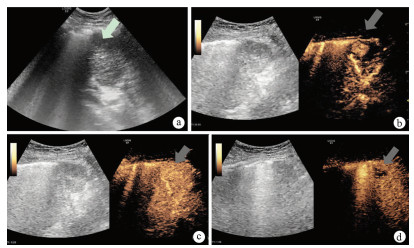

Expression of ASBT and ASGPR mediated receptors for oral liver-targeting preparations in a rat model of hepatic alveolar echinococcosis

Ruixue GAO, Chunhui HU, Fabin ZHANG, Pan GAO, Xuehui GAN, Yaogang ZHANG, Bofan JIANG

2021, 37(4): 846-851. DOI: 10.3969/j.issn.1001-5256.2021.04.024

Abstract(1291) HTML (348) PDF (3653KB)(67)

Abstract:

Objective  To investigate the feasibility of apical sodium-dependent bile salt transporter (ASBT) and asialoglycoprotein receptor (ASGPR) in the design of oral liver-targeting preparations for the treatment of hepatic alveolar echinococcosis (HAE) by measuring the expression of ASBT and ASGPR.  Methods  A total of 18 male Sprague-Dawley rats were selected, among which 10 were used to establish a model of HAE (HAE group) and 8 were used as controls (normal group). Immunofluorescence assay, Western blotting, and quantitative real-time PCR were used to measure the expression distribution, protein expression level, and mRNA expression level of ASBT in the ileal tissue of HAE model rats and normal rats; the same methods were used to measure the expression level of ASGPR in the non-diseased liver tissue and the marginal zone of liver tissue lesion of HAE model rats and the liver tissue of normal rats. The t-test was used for comparison of normally distributed continuous data between two groups; a one-way analysis of variance was used for comparison between three groups, and the least significant difference t-test was used for comparison between two groups.  Results  The results of immunofluorescence assay, Western blotting, and quantitative real-time PCR showed that compared with the normal group, the HAE group had significantly upregulated expression of ASBT in the ileal tissue (t=5.309, 4.110, and 28.060, all P < 0.05) and a significantly higher expression level of ASGPR (the closer to the lesion, the higher the expression) (F=110.666, 128.201, and 143.879, all P < 0.001).  Conclusion  ASBT and ASGPR can be used as potential mediated receptors for oral liver-targeting preparations for HAE, which provides a theoretical basis for the design of oral liver-targeting preparations for the treatment of HAE.